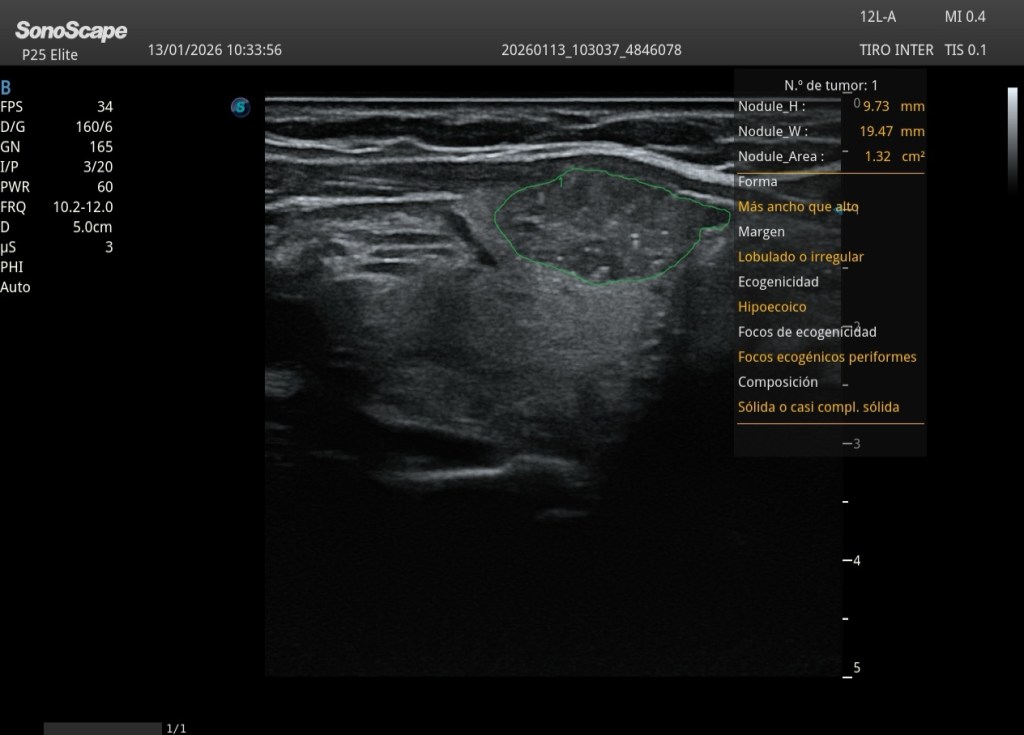

Identificación automática del nódulo tiroideo Delimitación de sus márgenes Obtención de medidas estándar y cálculo de área Análisis estructurado de los criterios ecográficos utilizados en sistemas de clasificación como ACR TI-RADS

El sistema TI-RADS (Thyroid Imaging Reporting and Data System) fue desarrollado para estratificar el riesgo de malignidad de los nódulos tiroideos a partir de hallazgos ecográficos estandarizados